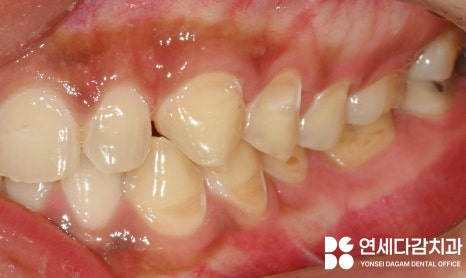

해당 사진을 보면 치아가

닳아 있는 형태를 띠고 있습니다.

그뿐만 아니라 심하면 마모를 넘어서

이렇게 치경부에

굴곡 파절이 생기기도 합니다.

해당 케이스는

평소 탄산음료를 즐겨 먹고,

역류성 식도염과

수면 중 이갈이 습관을 가졌을 때

나타난 구강 모습입니다.

이렇게 파절된 수준이 되면

상아질 구조가 드러나

이 시림 증세가 더욱 심해지게 됩니다.

그뿐만 아니라

어금니 부위에 교모증이 심해지면

교합이 깊게 맞물리면서

수직 고경이 낮아질 수 있습니다.

문정동 치과 에서 보여드리는

케이스도 낮아진 모습을 보이고 있는데요.